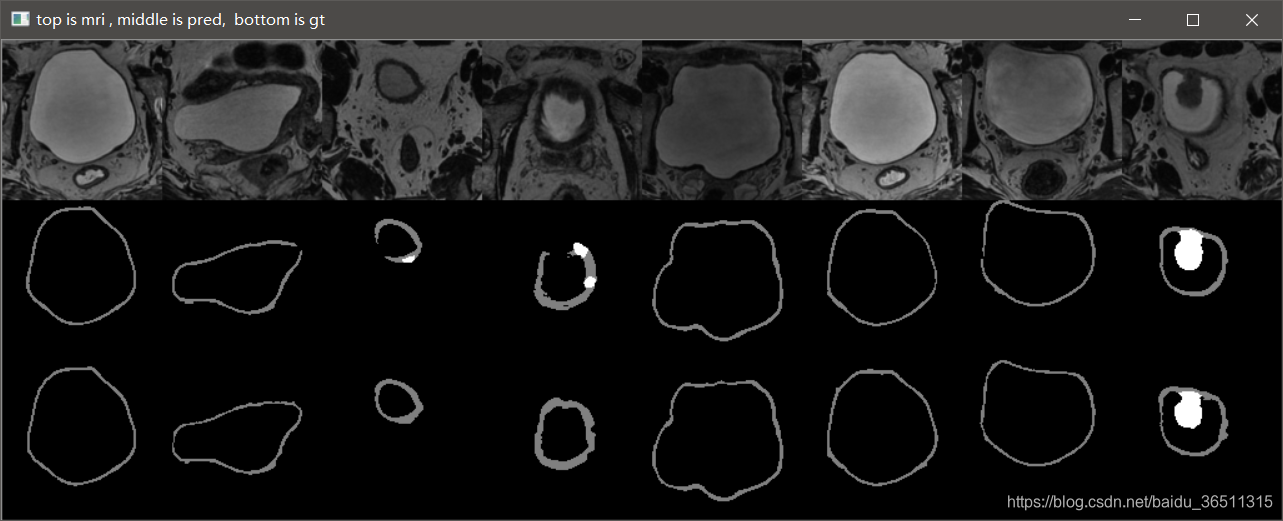

3.10 实验结果

这是笔记本跑了10个epoch的结果,仅仅是测试代码有没有问题。从结果可以看到,代码目前应该是没有问题的,后期只需调参数再训练提升效果即可。

GTX2080TI 跑120个epoch的测试效果:

Val Mean Dice = 0.9051, Val Bladder Dice = 0.9012, Val Tumor Dice = 0.9091